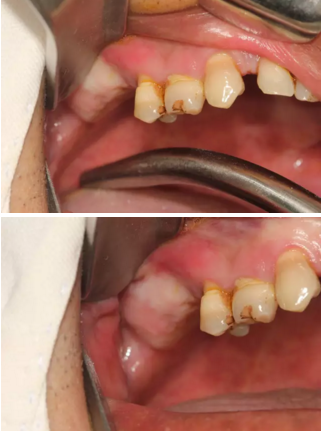

【病例分享】上頜竇大囊腫外提升